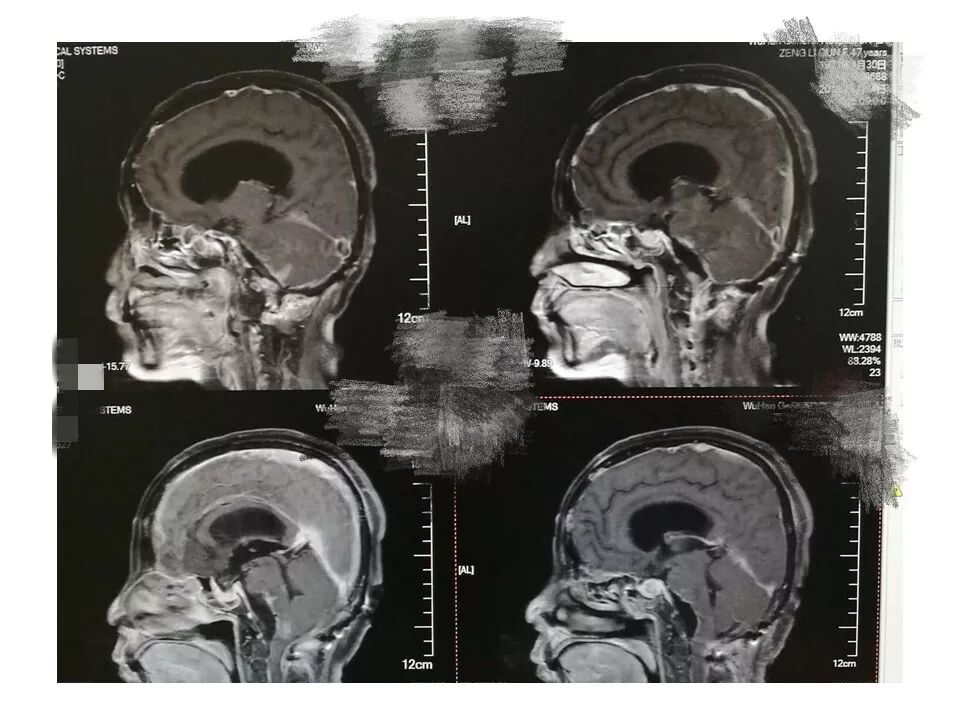

远外侧入路全斜坡巨大脑膜瘤显微手术1例